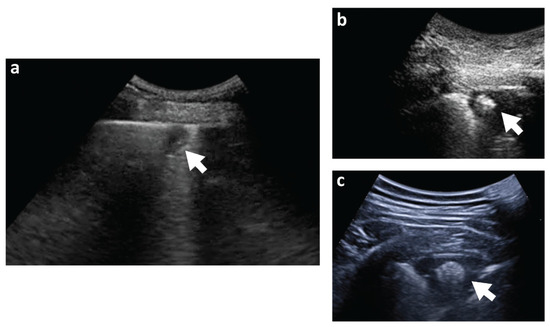

- Copetti, R.; Cominotto, F.; Meduri, S.; Orso, D. The “Survived Lung”: An Ultrasound Sign of “Bubbly Consolidation” Pulmonary Infarction. Ultrasound Med. Biol. 2020, 46, 2546–2550. [Google Scholar] [CrossRef]

- Raheja, R.; Brahmavar, M.; Joshi, D.; Raman, D. Application of Lung Ultrasound in Critical Care Setting: A Review. Cureus 2019, 11, e5233. [Google Scholar] [CrossRef] [Green Version]

- Squizzato, A.; Rancan, E.; Dentali, F.; Bonzini, M.; Guasti, L.; Steidl, L.; Mathis, G.; Ageno, W. Diagnostic accuracy of lung ultrasound for pulmonary embolism: A systematic review and meta-analysis. J. Thromb. Haemost. 2013, 11, 1269–1278. [Google Scholar] [CrossRef]

- Baz, A.A.; Hamdy, I.M.; Mohammed, A.S.; Assal, H.H. Diagnostic validity of thoracic ultrasound in the assessment of pulmonary embolism. Egypt. J. Radiol. Nucl. Med. 2019, 50, 5. [Google Scholar] [CrossRef] [Green Version]